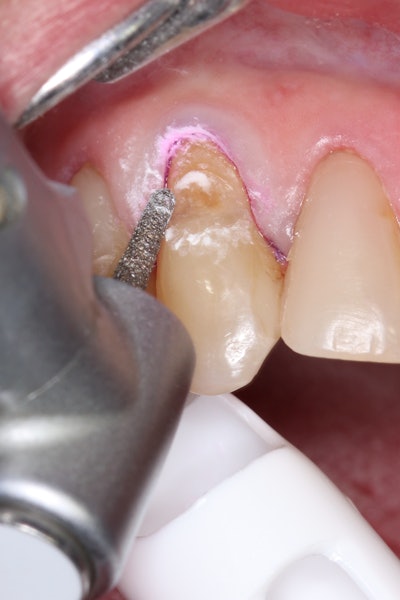

Caries detection and preparation

To improve isolation and soft-tissue access, a retraction cord was placed before initiating the procedure (Figure 2).

Figure 2: Placement of a retraction cord to improve isolation and access to the cervical area prior to preparation.Figure 2: Placement of a retraction cord to improve isolation and access to the cervical area prior to preparation.

Decay removal was completed with a diamond bur, and the enamel was beveled using a starburst pattern to enhance aesthetic blending (Figure 4). This preparation design was chosen for visual integration rather than bond strength enhancement.

Figure 4: Preparation of the lesion completed with a diamond bur and starburst beveling pattern to enhance aesthetic blending.Figure 4: Preparation of the lesion completed with a diamond bur and starburst beveling pattern to enhance aesthetic blending.